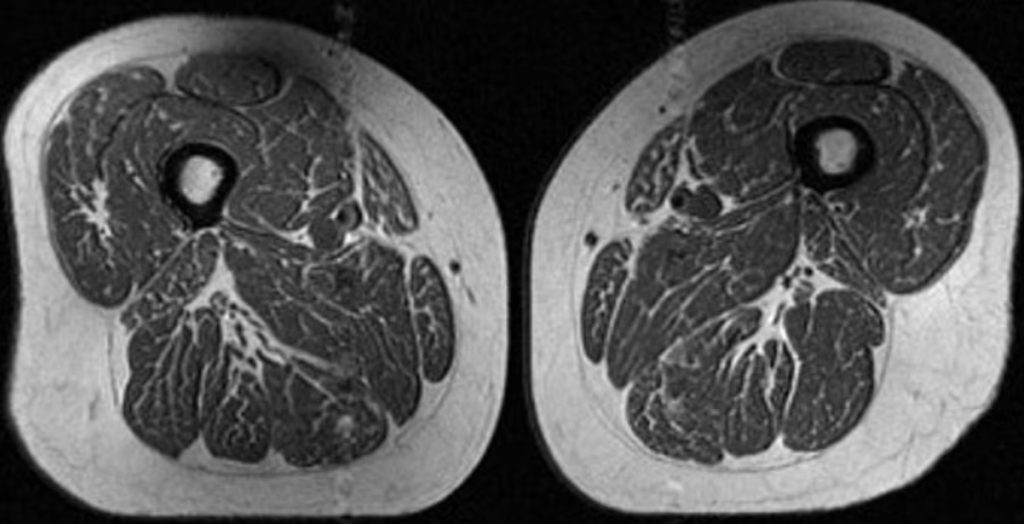

Η εικόνα που εξετάζουν οι ερευνητές δεν είναι ωστόσο φαγητό. Πρόκειται για μαγνητική τομογραφία (MRI) του μηρού μιας 62χρονης γυναίκας, η οποία αντλούσε το 87% των ετήσιων θερμίδων της από υπερεπεξεργασμένα τρόφιμα.

Στη μελέτη, μια δεύτερη γυναίκα 61 ετών εμφάνισε επίσης λιπώδη διήθηση στους μηρούς, αλλά σε μικρότερο βαθμό, με το 29% της διατροφής της να προέρχεται από υπερεπεξεργασμένα τρόφιμα.

«Ήταν ιδιαίτερα ανησυχητικό, επειδή αυτά τα άτομα, τα οποία εξετάστηκαν τη στιγμή που δεν είχαν σημάδια οστεοαρθρίτιδας γόνατος, ήδη εμφάνιζαν μειωμένη ποιότητα μυών», δήλωσε η Akkaya.